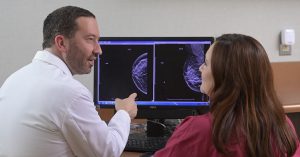

If you’ve been diagnosed with breast cancer, you shouldn’t despair. Modern medicine has effective treatments for breast cancer. It is a complex and complex process that includes the use of chemotherapy, radiation therapy, and surgery. Depending on the stage of cancer development and your condition, the doctor chooses the methods of treatment and stages of treatment.